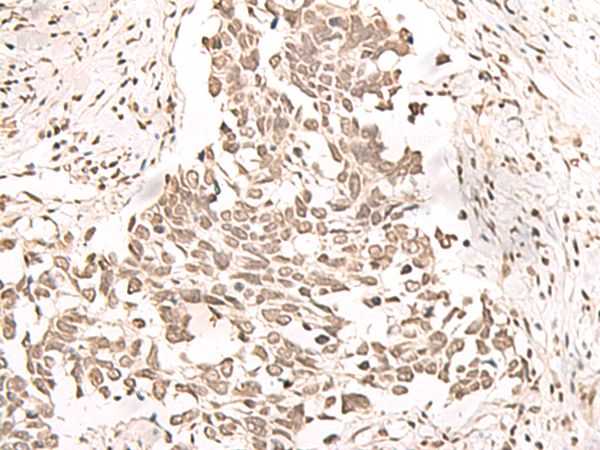

The image is immunohistochemistry of paraffin-embedded Human lung cancer tissue using 47252(RRP1 Antibody) at dilution 1/40.(Original magnification: 200)